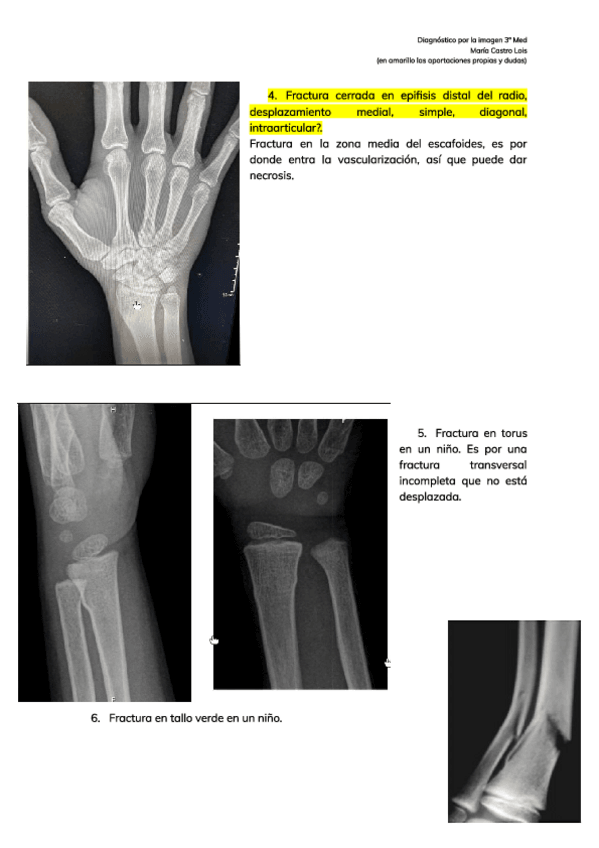

He publicado nuevos apuntes de 3º Introducción a la Cirugía, Medicina preoperatoria: seminario-MK.pdf

17 páginas